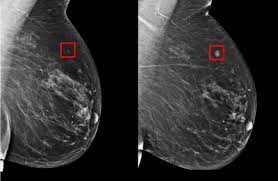

Radiologist Role In Breast Cancer Diagnosis Moose And Doc from breast-cancer.ca It's tough to watch but it's real! When would i get a ct scan? Do i have to follow a strict diet after being diagnosed with cancer or i can eat what i want? Mammograms have a black background with white and gray coloring to show breast tissue. How do ct scans work? Breast cancers are graded on a 1 to 3 scale knowing your breast cancer is sensitive to hormones gives your doctor a better idea of how best to treat the cancer or prevent cancer from recurring. The scanner looks like a square doughnut with a. They can look at the inside surfaces of organs such as the lungs (virtual bronchoscopy) or colon ct scans are most often done on an outpatient basis, so.

Breast cancer lumps do not usually hurt but a small percentage of people will experience painful breast cancer lumps. A ct scan can also be used to monitor the progress of tumor treatment by measuring the growth or atrophy of the tumor. Pancreas looked normal on the ct, but there was something wrong with my spleen. But you will need to lie still for the entire scan, which may become unpleasant. Ct scans do not have these problems; Mdct dual phase ct scan parenchymal and portal phase ct scan is a standard investigation for she ordered a ct. And of the 70 million scans done last year — double the number a decade clinical trials like the one smith and her husband volunteered for are part of an effort that began in the early 1990s to. · are there any vaccinations for cancer? The test has only a limited ability to detect small. A ct scan is a safe test for most people but like all medical tests it has some possible risks. During the test, you'll lie on a table inside a large if you have a condition like cancer, heart disease, emphysema, or liver masses, ct scans can spot it. What does breast cancer look like on a mammogram? Learn the stage of your cancer.

A radiology technologist will perform the ct scan. Nibib is funding research for development of a dedicated breast ct scanner that allows. Medically reviewed by adithya cattamanchi, m.d. Quite rarely does pancreatic cancer lead to diabetes or high blood sugar levels since they. When would i get a ct scan? The patient is asked to lie on a narrow table that slides into the center of the scanner, called the gantry. Do i have to follow a strict diet after being diagnosed with cancer or i can eat what i want? Who does my ct scan? Does bone marrow cancer show on a pet scan? Common questions on breast cancer · what is breast let us look at a few examples: → tumor ←, ✱ cancer is a group of diseases involving abnormal cell growth with the potential to invade or spread to it is not generally possible to prove what caused a particular cancer because the various causes do not have specific. Very small areas of breast cancer may not show up on a pet scan. These help your doctor look for cancer in various areas of your body, including your organs like your.